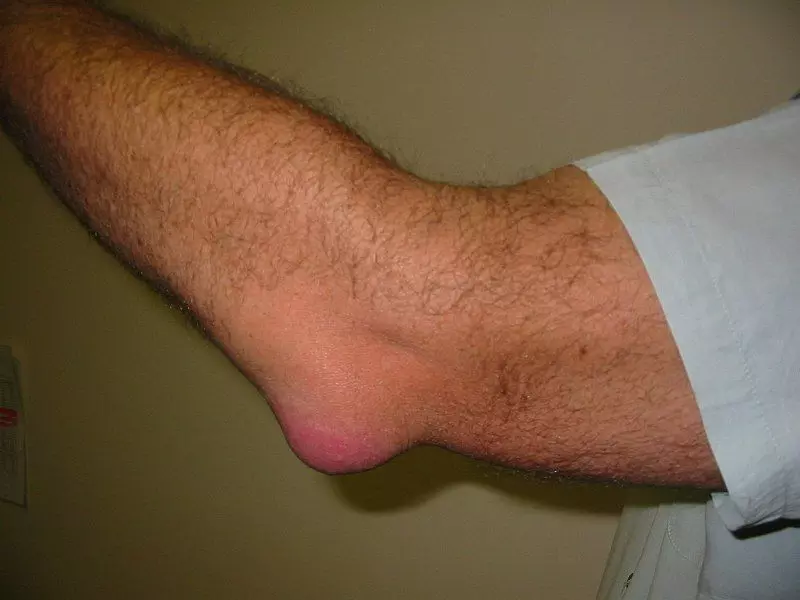

Image - A patient with olecranon bursitis

Creative commons source by en:User:NJC123 [CC BY-SA 4.0 (https://creativecommons.org/licenses/by-sa/4.0)]

Olecranon bursitis, also known as ‘Student’s elbow’, is inflammation of the olecranon bursa. It is often due to repeated micro-trauma such as leaning on the elbow whilst studying. The swelling is usually soft, filled with serous fluid and transilluminates (unless it is septic bursitis).

Treatment involves avoiding direct pressure on the olecranon bursa or wearing a pad to cushion the bursa, as well as taking NSAIDs such as ibuprofen to reduce pain and swelling. It is however often only a cosmetic abnormality and causes no pain. If septic bursitis is present, antibiotics need to be given, possibly with an aspiration of the fluid.